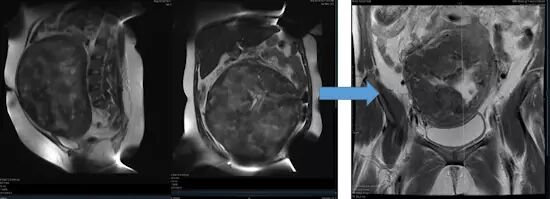

图 4 为 34 岁女性有严重的月经过多和贫血,腹部 MR 示一巨大单发 30*20 cm 肌瘤。医生建议其接受子宫切除术,但她选择肌瘤栓塞术。术后肌瘤体积减小 60%,症状得到控制